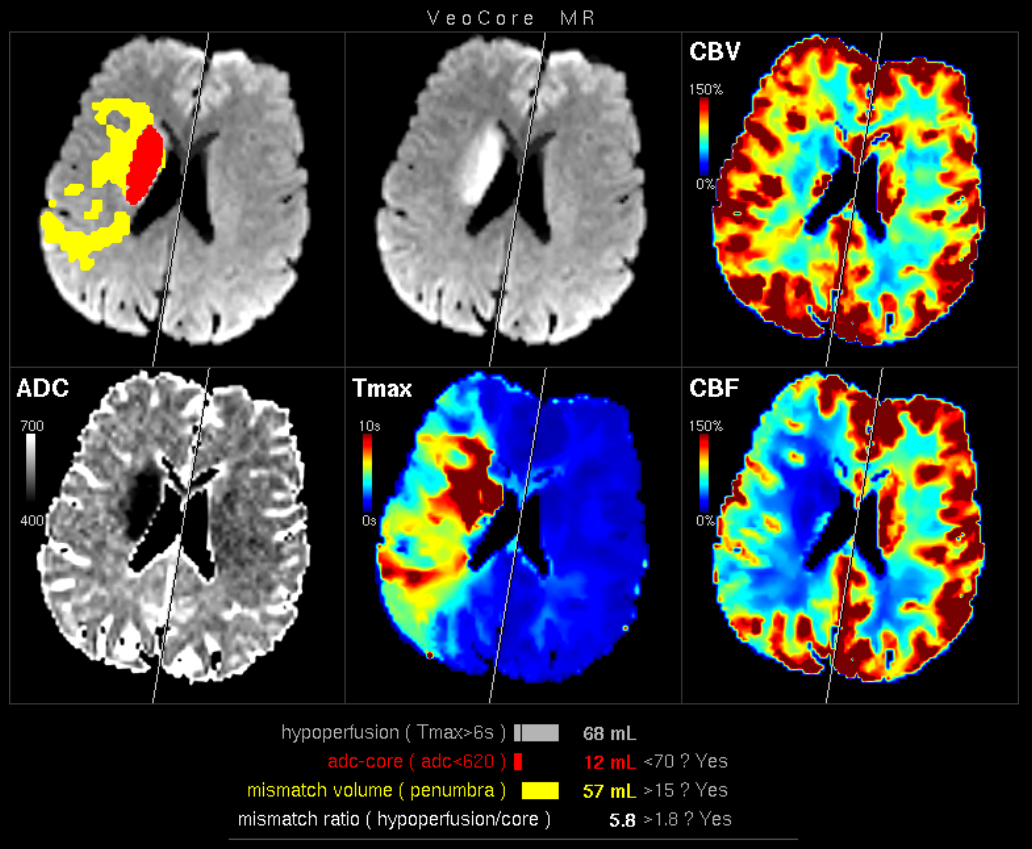

Furthermore mRay is capable of performing image processing tasks such as finding, visualizing and quantifying anomalies in tissue. In particular the image analysis module mRay VEOcore may be used to perform an automated processing of brain images from imaging modalities such as CT, CT-Perfusion, or MRI including a Diffusion Weighted Imaging (DWI) Module. As a result, changes in contrast over time are visualized as colored perfusion maps, including flow related parameters and tissue blood volume quantification.

The perfusion analysis of brain imaging data visualizes and quantifies tissue that is less supplied with blood (penumbra), oxygen deprived tissue caused by obstructed blood flow (core tissue) and the mismatch ratio between the two. The calculated values can be used to support decision making based on an assessment of the extent of tissue damage.

16.1. Overview

VEOcore is a fully automated image processing tool to calculate quantitative measures of affected brain tissue and healthy tissue. Therefore, this manual covers the instructions on how to interpret the results. It’s an extension the mRay Server application and the results can be viewed inside the mRay Client. Furthermore processed results can be automatically forwarded to the PACS.

16.2.2. Magnetic Resonance Imaging (MRI)

-

MR perfusion (DSC-Perfusion) (optional)

Repeatedly acquired volumes of echo-planar imaging acquired during injection of a contrast bolus. This measurement technique is often referred to as DSC-Perfusion (Dynamic-susceptibility-contrast perfusion). Sending a perfusion measurement is optional in MR. If not send, only the infarction core will be segmented based on the ADC (see below). -

MR ADC

Apparent-Diffusion-Coefficient (ADC), berechnet aus einer diffusions-gewichteten Sequenz (DWI-MR). Das senden des direkt am MR-Scanner berechneten ADC ist unbedingt notwendigan ADC, VEOcore berechent keinen ADC selbst aus den DWI-Daten. -